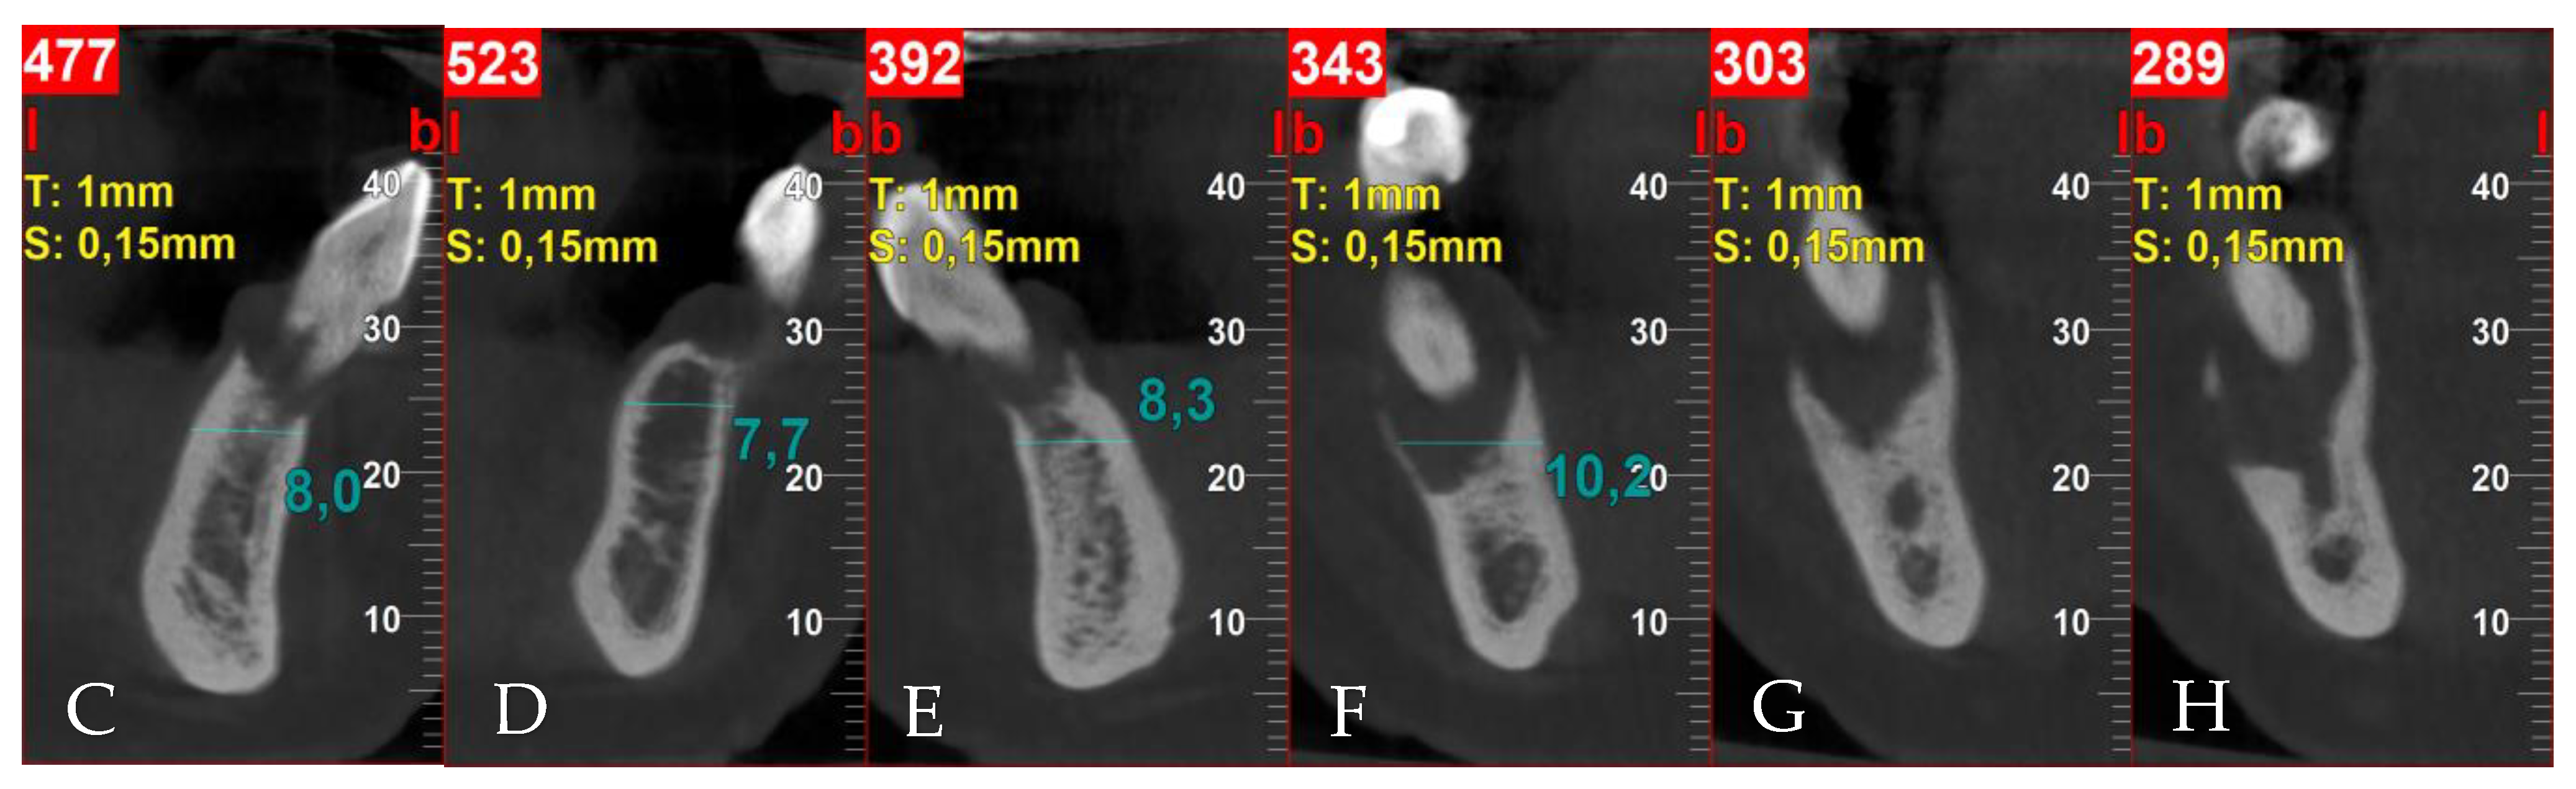

3.1. Patient Information, Diagnosis and Treatment Plan

3.2. Surgery 1—Teeth Extraction and Periodontal Lesion Enucleation with Simultaneous Implantation